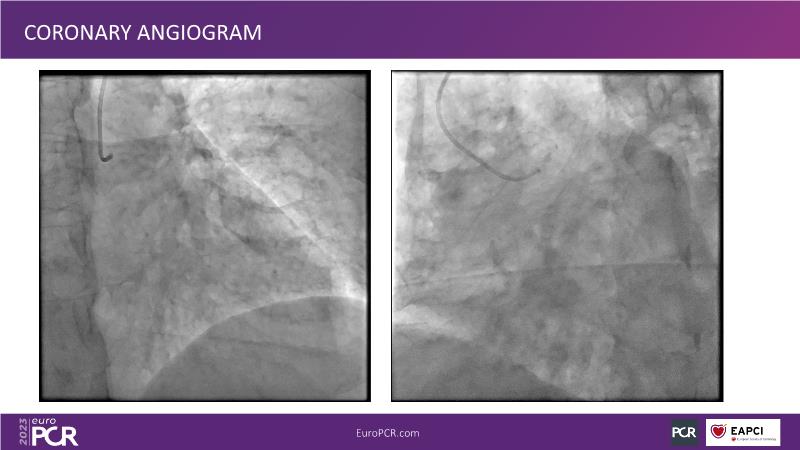

In this session focused on epicardial and microcirculatory dysfunction, discuss how to treat both a 72-year-old smoker man with HTN, diabetes, hyperlipidemia, who presented with angina and dyspnea with moderate exertion over the last months, and a 69-year-old ex-smoker man with HTN and untreated LDL 125 mg/dl who presented with chest pain of unknown origin started about 6 months ago and shortness of breath on exertion.

- To understand how a stepwise physiological approach can identify the cause of angina in your patient, with or without obstructive disease